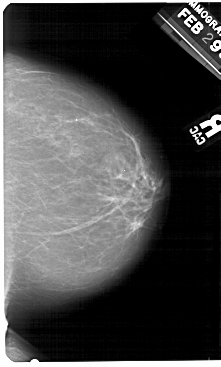

A_1493_1.RIGHT_MLO

RIGHT_MLO LINES 5491 PIXELS_PER_LINE 3556 BITS_PER_PIXEL 12 RESOLUTION 43.5 NON_OVERLAY